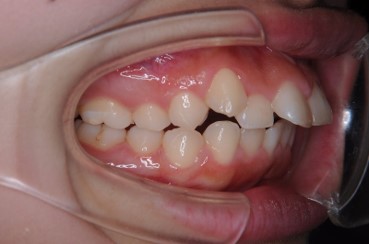

【症例】叢生の治療(でこぼこ、凹凸、ガタガタの治療)

- 治療前

- 治療後

- 治療名

- 叢生の治療(でこぼこ、凹凸、ガタガタの治療)

- 費用

- 検査費 40,000円(税抜) 、

治療費用 820,000円(税抜) (トータルフィー)

- 期間

-

30ヶ月(2年6ヵ月)

治療内容

患者様の症状

右上の八重歯と、歯並びのでこぼこを治したいと希望して来院されました。セファロ(横顔のレントゲン)分析より、上下のあごのバランスは良い状態で、上下の前歯がやや前方に出ている状態でした

治療法

上下左右の小臼歯を一本ずつ抜歯して八重歯を治したり前歯を後退させたりするスペースを作って、マルチブラケット装置により歯の移動を行い、かみ合わせを整えました。

治療結果

治療後は上下の歯がしっかりかみ合いました。

※治療結果は患者様によって個人差があります。

治療を行う上での 注意点 (リスク・副作用)

歯を移動する量が大きくなると、歯根吸収(根が短くなること)や歯肉退縮(歯ぐきの下がり)のリスクが高くなります。歯磨きが悪いと、歯の変色や虫歯の危険性が高くなりますが、ブラッシング状況もよく、きれいな歯が維持できました。